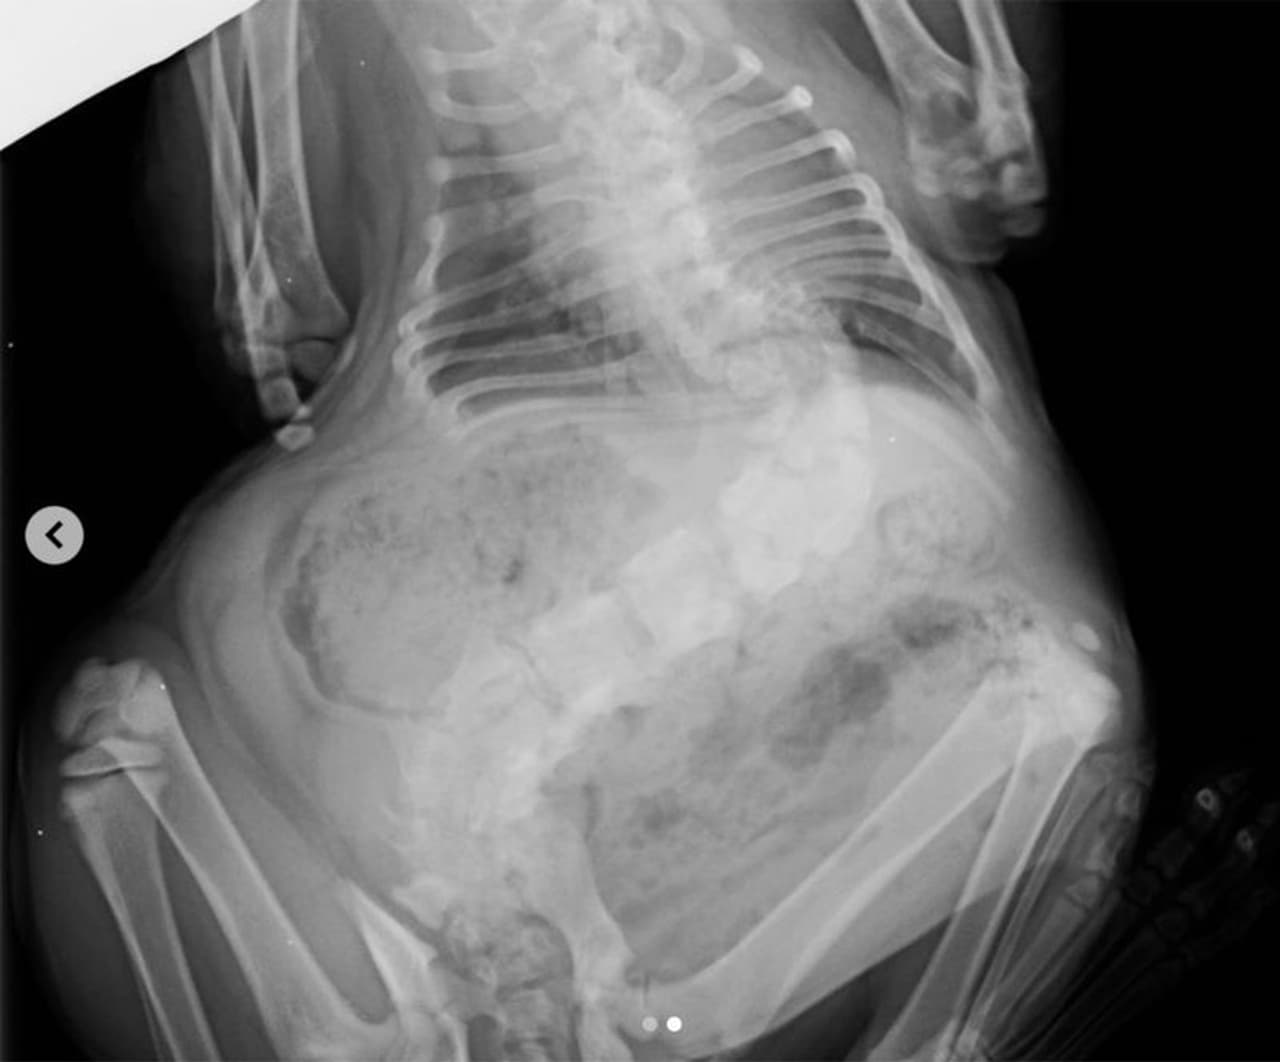

നട്ടെല്ലിന് കാര്യമായ വളവുണ്ട്. തടി പതിവിലും എത്രയോ ഓവറാണ്. എന്നാലെന്താ? സുന്ദരമായൊരു മുഖമില്ലേ പിറ്റോയ്ക്ക്? പിറ്റോ ആരാണെന്നോ? ബ്രിട്ടീഷ് ഷോർട്ട് ഹെയർ എന്ന ഇനത്തിൽ പെട്ട ഒരു പെഡിഗ്രീഡ് പൂച്ചയാണ് നാലുവയസ്സുകാരനായ പിറ്റോ. സ്കോളിയോസിസ് എന്നൊരു ജനിതകരോഗത്തിന് അടിമയാണ് പിറ്റോ. നട്ടെല്ല് വല്ലാതെ വളഞ്ഞു പോകുന്ന ഒരു രോഗമാണ് സ്കോളിയോസിസ്. ഈ രോഗം ബാധിക്കുന്ന പൂച്ചകൾക്ക് മറ്റുള്ള പൂച്ചകളെക്കാൾ നീളവും ഉയരവും ഒക്കെ കുറവാകും. പതിവിൽ കവിഞ്ഞ തടി തോന്നിക്കുകയും ചെയ്യും.

ഇങ്ങനെ വിലക്ഷണമായി പിറന്നുവീണ പിറ്റോയെ പരിചരിക്കാൻ ബുദ്ധിമുട്ടുള്ളതുകൊണ്ട് അവനെ ദയാവധത്തിന് വിധേയനാക്കാൻ വേണ്ടിയാണ് വെറ്ററിനറി ക്ലിനിക്കിലേക്ക് കൊണ്ടുവന്നത്. എന്നാൽ, പിറ്റോയുടെ നോട്ടം കരളിൽ തറച്ചുപോയ ആ ഡോക്ടർക്ക് അവനെ എന്തോ വിഷം കുത്തിവെച്ച് കൊന്നുകളയാൻ മനസ്സുവന്നില്ല. " പിറ്റോയെ എനിക്ക് തന്നോളൂ.. ഇവനെ കൊല്ലാൻ എനിക്കാവുന്നില്ല.